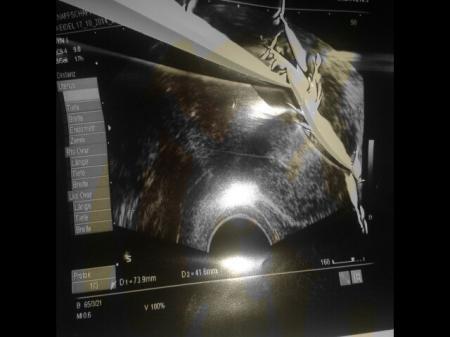

Hier noch eins sieht man da wahrscheinlich besser... Was kann der winzig kleine ovale schwarze kreis in meiner gebärmutter noch sein? Wenn ich nicht schwanger bin?

Bild zu

Vor Mens Termin sieht man definitiv keine fruchthöhle im Ultraschall! Unmöglich. Meist erst so bei 4+2-4+4. alles sehr kurios bei dir

Ja und was soll ich jetzt tun? Ich kann ihn nicht wegzaubern.... es war so auf dem US und ich hätte es erst gar nicht gesehen hätte mein arzt mir das nicht gezeigt... Er sagte abwarten... und bei meinen andern 3 kindern habe ich 3 tage vor fälligkeit schon ne frichthöhle gehabt die definitiv um einiges größer war als das was jetzt da drin ist... Ich wollte nur wissen was das sonst noch sein kann... weil ich denke nicht wirklich dass es ne fruchthöhle ist..dafür wars viiel zu klein...

Ich wollte doch nur wissen was das eventuell sein kann? Vielleicht hattet ihr ja auch mal so einen schwarzen punkt... Weil für ne fruchthöhle wie gesagt ist es viel zu klein...